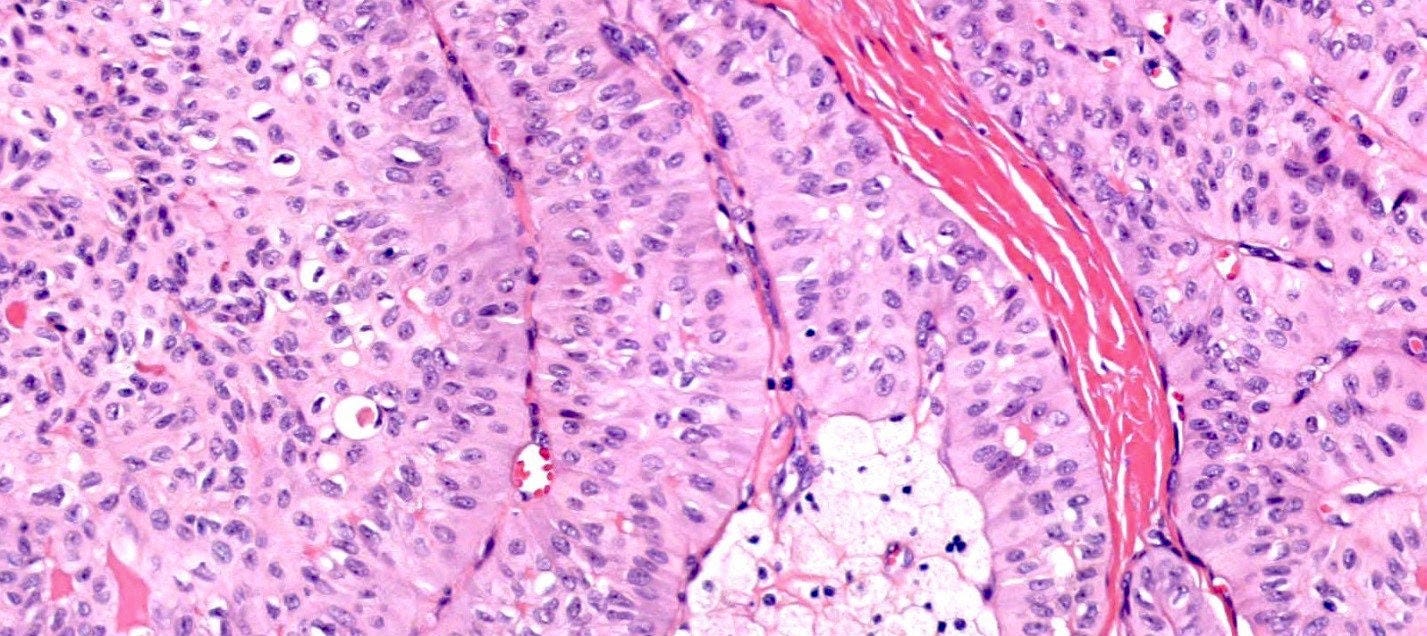

Medullary carcinoma of the breast is a rare subtype (3 - 5%) of invasive breast cancer with pushing borders, syncytial growth, high grade nuclei and a prominent lymphoid infiltrate. According to the World Health Organization, the preferred terminology is invasive breast carcinoma of no special type with medullary pattern.

Microscopically, medullary carcinoma is composed of large, pleomorphic, high grade tumor cells arranged in broad syncytial sheets occupying at least 75% of the tumor area. The tumor cells have vesicular nuclei (i.e., large, pale staining with a central clearing) with prominent nucleoli and abundant eosinophilic cytoplasm. A prominent and dense lymphoplasmacytic infiltrate surrounds and often infiltrates the tumor, suggesting a vigorous host immune response. Mitotic figures are numerous and areas of necrosis may be present.

Immunohistochemically, medullary carcinomas typically show a triple negative phenotype (i.e., negative for ER, PR and HER2). However, they frequently express basal cytokeratins such as CK5/6 and epidermal growth factor receptor (EGFR), aligning them with the basal-like molecular subtype. Molecular studies reveal frequent TP53 mutations and a strong association with germline BRCA1 mutations, particularly in patients under 50 years of age or those with a family history of breast or ovarian cancer. Medullary carcinoma shows significant genomic instability with frequent chromosomal aberrations.

Medullary carcinoma - radiologic and microscopic images